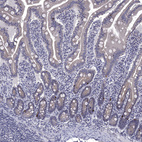

Immunohistochemistry analysis in human small intestine and liver tissues using HPA040591 antibody. Corresponding HTR4 RNA-seq data are presented for the same tissues.